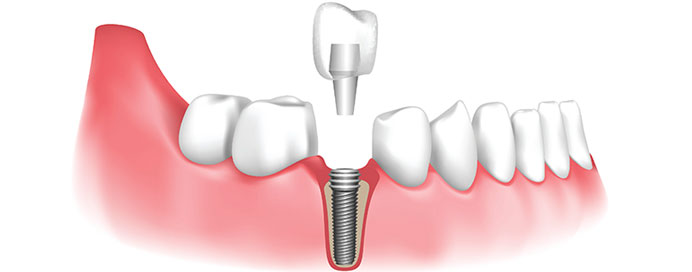

Dental implants are a modern and highly effective solution for replacing missing teeth. They consist of a small titanium post surgically placed into the jawbone, which acts as a replacement root for a missing tooth. Once the implant integrates with the bone through a process called osseointegration, a crown, bridge, or denture is attached to restore the function and appearance of the tooth. Dental implants provide a durable, long-lasting, and natural-looking option for restoring smiles and maintaining oral health. They help prevent bone loss in the jaw, improve chewing and speech, and enhance overall confidence. Implants are suitable for single tooth replacements, multiple missing teeth, or even full-arch restorations with implant-supported dentures. With proper care and regular dental check-ups, implants can last a lifetime, making them a preferred choice for many patients.